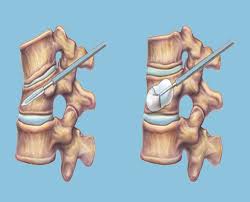

Cervical myelopathy, spinal stenosis, and herniated discs can all be...

Read More